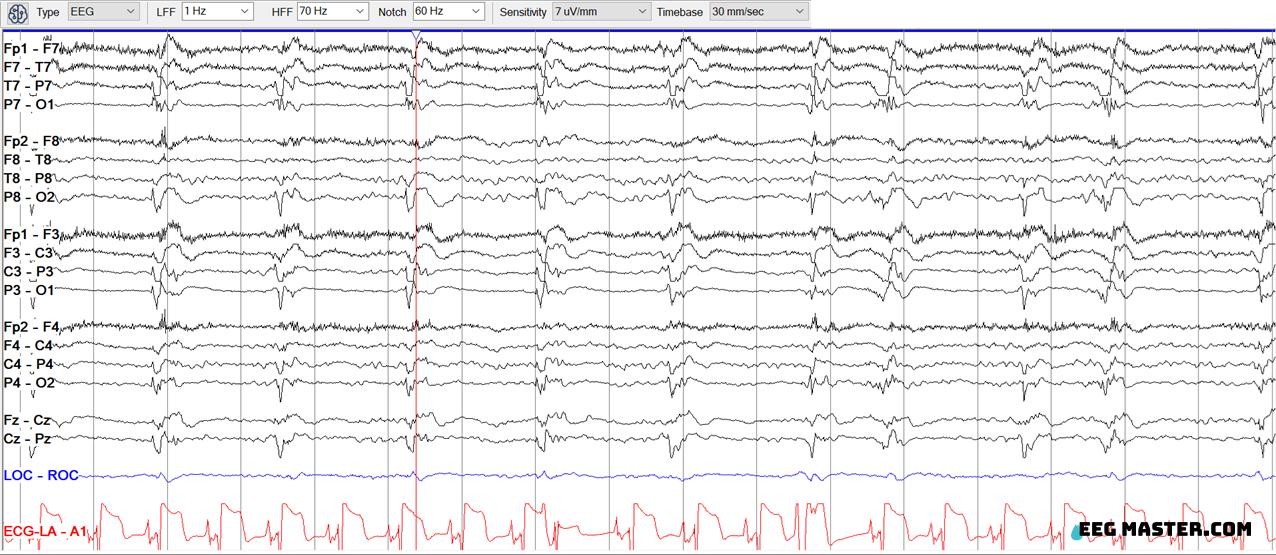

The following EEG shows a pattern that would qualify as part of the Ictal-Interictal Continuum. Choose the pattern and the criteria it meets